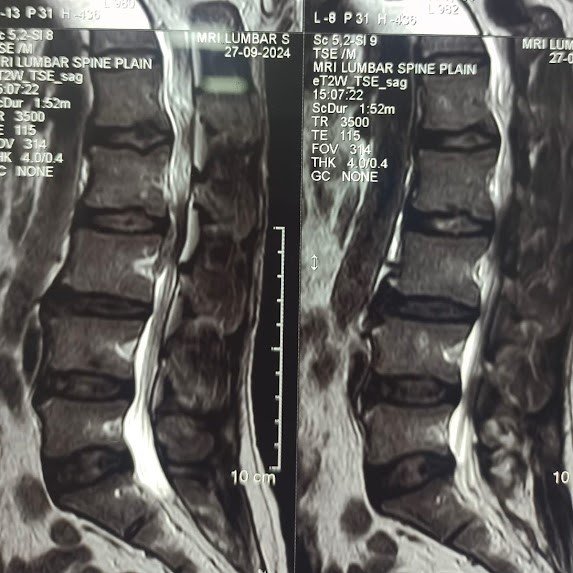

Posted on Nilesh KaduTrustindex verifies that the original source of the review is Google. I visited Dr. Nitish Agarwal for my severe back pain and shoulder issue. He checked my MRI very carefully and gave the perfect diagnosis. Yesterday, he performed the procedure (Root Block and Shoulder Injection), and it was completely painless. He is an expert and targeted the exact nerve point causing the trouble. Very helpful and humble doctor. Highly recommended for anyone with spine problems.Posted on Raju GorkhaTrustindex verifies that the original source of the review is Google. I was unable to make movement and suffered from right foot drop which is equal to halfway paralysis. Dr. Nitish Agarwal performed very fine microscopic surgery on L3, L4 & L5. After 90 days under his treatment I could go for a walk min. 6 kms a day, I have started my regular activities after 120 days. Thank you so much Dr. Nitish Agarwal sir.Posted on Pururaj GuravTrustindex verifies that the original source of the review is Google. I was suffering from severe back pain, and Dr. Nitish Agrawal has been extremely supportive throughout my treatment. He listened carefully, explained everything clearly, and guided me very well. His treatment has really helped me recover. He is one of the best spine specialists — highly recommended!Posted on Vinal AgrawalTrustindex verifies that the original source of the review is Google. I had consulted many doctors before Dr Nitish for my mother's spine issue,most recommended complex procedures and surgeries. Fortunately we found Dr Nitish and it has been life changing for my mother,she was in immense pain before the simple surgery he did. It's rare to find a surgeon who explains everything in detail and provides such exceptional care even after the surgery. I Would highly recommend him.Posted on Ajinkya MohadkarTrustindex verifies that the original source of the review is Google. My mother had sustained a fracture to her right hand wrist and we were worried about her recovery due to age factor. One of our family Doctor referred us to Dr. Nitish Agrawal and we visited Dr. Nitish Sir. Dr. Nitish sir ensured that my mother don't need a surgery and treated her by application of plaster (temporary and then cast-iron or Firm plaster) with certain orthopaedic treatment to hand and prescribed oral medication for ensuring recovery is faster without any surgery. Attaching the photo of xray which shows recovery of wrist bone which has rejoined and we are still continuing treatment to ensure my mother is fully recovered and is fit. Thank you Dr.Nitish Agrawal for your support.Posted on Samadhan LokhandeTrustindex verifies that the original source of the review is Google. Hi everyone, myself Samadhan. I was suffering from severe spine pain for a long time, and one of my friends suggested I visit Dr. Nitish Agarwal. Honestly, that was the best advice! Dr. Nitish listened to my problem very patiently, explained the cause in detail, and gave me the right treatment. I started feeling better within a short time. He is very polite, knowledgeable, and truly cares for his patients. I highly recommend Dr. Nitish Agarwal for anyone dealing with spine or back pain. Thank you, doctor, for your excellent treatment and support!Posted on POOJA JAGDALETrustindex verifies that the original source of the review is Google. Dr. Nitish Agrawal is an excellent spine specialist who patiently listens, explains the problem clearly, and provides the best treatment options.Posted on vipul pardeshiTrustindex verifies that the original source of the review is Google. Dr.Nitish sir is an incredible surgeon. I had excellent results from my recent spine surgery. The entire process, from consultation to recovery, was handled with professionalism and care. The outcome has been life-changing. I highly recommend Dr.Nitish agarwal to anyone in need of a spine surgeon.Posted on Deepak JadhavTrustindex verifies that the original source of the review is Google. A few months back I took treatment for my back pain from dr. Agarwal sir ...last 7-8 years i was suffering with low back pain,unbale to stand for more than 10 minutes..My low back hurts continuously, and also left leg pain was unbearable....i try every possible way of treatment from various suggestion...After several treatment...one of my relative suggested dr. Nitish Agarwal sirs name then I visited Dr. Nitish Agarwal sir in clinic. He suggested me x ray and MRI. On that basis he advise me caudal Block with root block with facet block for pain management. After block my pain goes with in a week. He advise me regular Physiotherapy at home. Now after regular exercise I am pain Free. Dr. Nitish Agarwal is a good doctor for any spine related problem.... Thank u dr. Agarwal Sir 🙏Posted on Kumar BTrustindex verifies that the original source of the review is Google. My wife had major infection in neck and lower back. She was bedridden. her legs and hands were weak. Then we admit her under Dr. Nitish Agarwal sir and did MRI. He explained that she is having major infection in cervical and lumbar spine. Due to infection her spinal cord is compressed so she was not able to walk. Then sir did operation for neck and removed infected tissue and spinal cord is freed and put a plate. Her lower back is treated with medicine only. She was given 2 months antibiotics by saline and 5 months oral antibiotics were given. He also advised regular exercise. After 15 days of surgery she started walking with support. Now after 1 year she is completely alright and walking like a normal person. She is regularly doing all her activities. Now she can also travel by 2 wheeler. Thank you to Dr. Nitish Agarwal sir for his expert work in spine. I recommend Dr. Nitish Agarwal for any spine related problem.